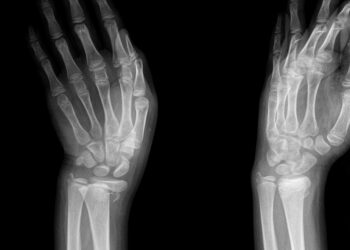

Kienböcko liga: simptomai, priežastys ir gydymas

Kienböcko liga – tai reta būklė, kai po truputį nyksta mėnulio formos kaulas rieše, vadinamas lunatum. Ligai progresuojant, gali suprastėti...